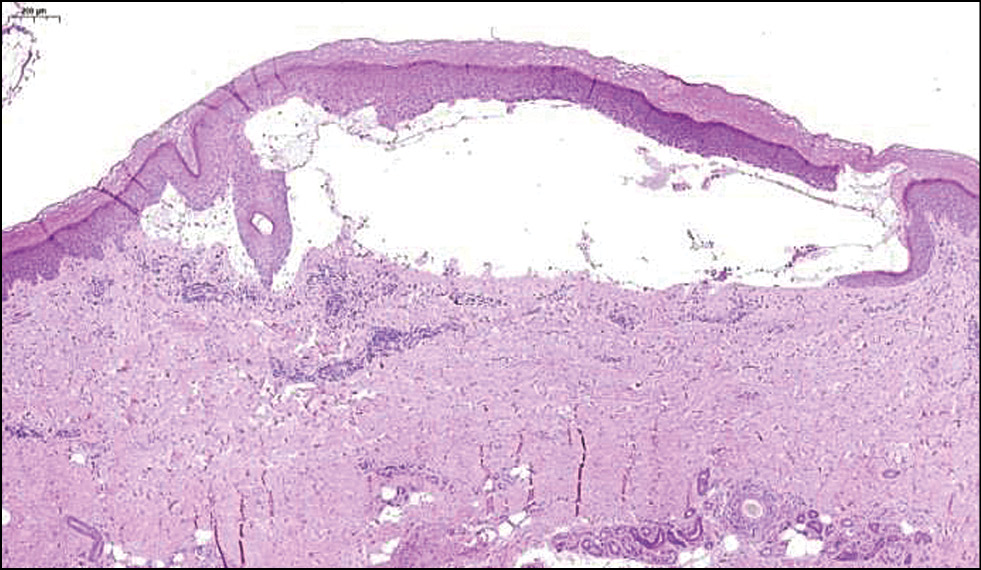

Результаты физикального, лабораторного и инструментального исследования. При постановке реакции иммунофлюоресценции определяется линейное отложение IgG, IgM вдоль базальной мембраны. В реакциях с антителами IgA свечения нет (рис. 2). При гистохимическом исследовании обнаружены субэпидермальные пузыри, состоящие из малодифференцированных фибробластов; в верхней части дермы и утолщённых стенках капилляров имеются отложения гиалина (рис. 3). В стенках сосудов выявлены ШИК*-положительные диастазорезистентные вещества (рис. 4).

Рис. 3. Результаты гистохимического исследования кожи: отложения гиалина в верхней части дермы и утолщённых стенках капилляров. ×50. / Fig. 3. Results of histochemical assay of the skin: hyaline deposits in the upper part of the dermis and thickened capillary walls. ×50.

Другим инструментом служит биопсия кожи, которая обычно не требуется для диагностики данного заболевания, но помогает при дифференциальной диагностике. При этом в литературных источниках сообщается, что результатом данного исследования при кожных порфириях, как правило, является гистологическая картина субэпидермальных пузырей и отложений иммунных комплексов [9], что соответствует гистологической картине результатов биопсии пациента в представленном клиническом случае.